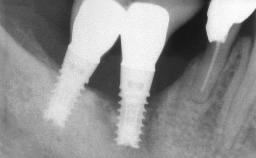

The fracture of an implant after it has been restored is one of the most severe complications. It most frequently occurs in partially edentulous jaws (1.5%). Most implant fractures involve implants with a diameter of 3.75 mm made of commercially pure titanium (Eckert 2010). Unfortunately, many cases are not reported or documented by the clinicians involved in resolving the problems created by the fracture. This case report describes the management of an implant fracture at site 36 in a middle-aged male patient. The implant had been restored with a screw-retained metal-ceramic crown.

Case Type Single-Tooth Space

Jaw Mandible

Area Posterior

# of Teeth 1

# of Implants 1

Type of Implants Two-Piece